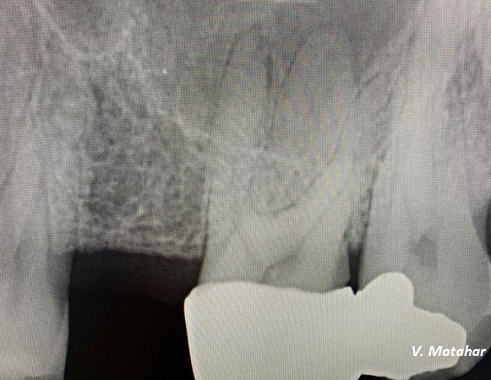

Root canal treatment on three rooted tooth! which had 4 canals!